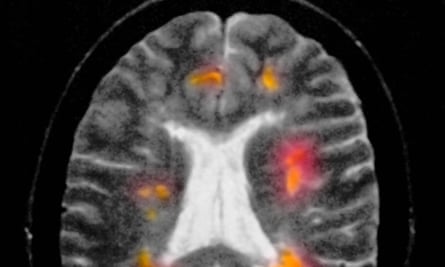

Funded by the MS Society, bexarotene was assessed in a phase 2a trial that used brain scans to monitor changes to damaged neurons in patients with relapsing MS. This is an early stage of the condition that precedes secondary progressive disease, where neurons die off and cause permanent disability.

The drug had some serious side-effects, from thyroid disease to raised levels of fats in the blood, which can lead to dangerous inflammation of the pancreas. But brain scans revealed that neurons had regrown their myelin sheaths, a finding confirmed by tests that showed signals sent from the retina to the visual cortex at the back of the brain had quickened. “That can only be achieved through remyelination,” said Coles.